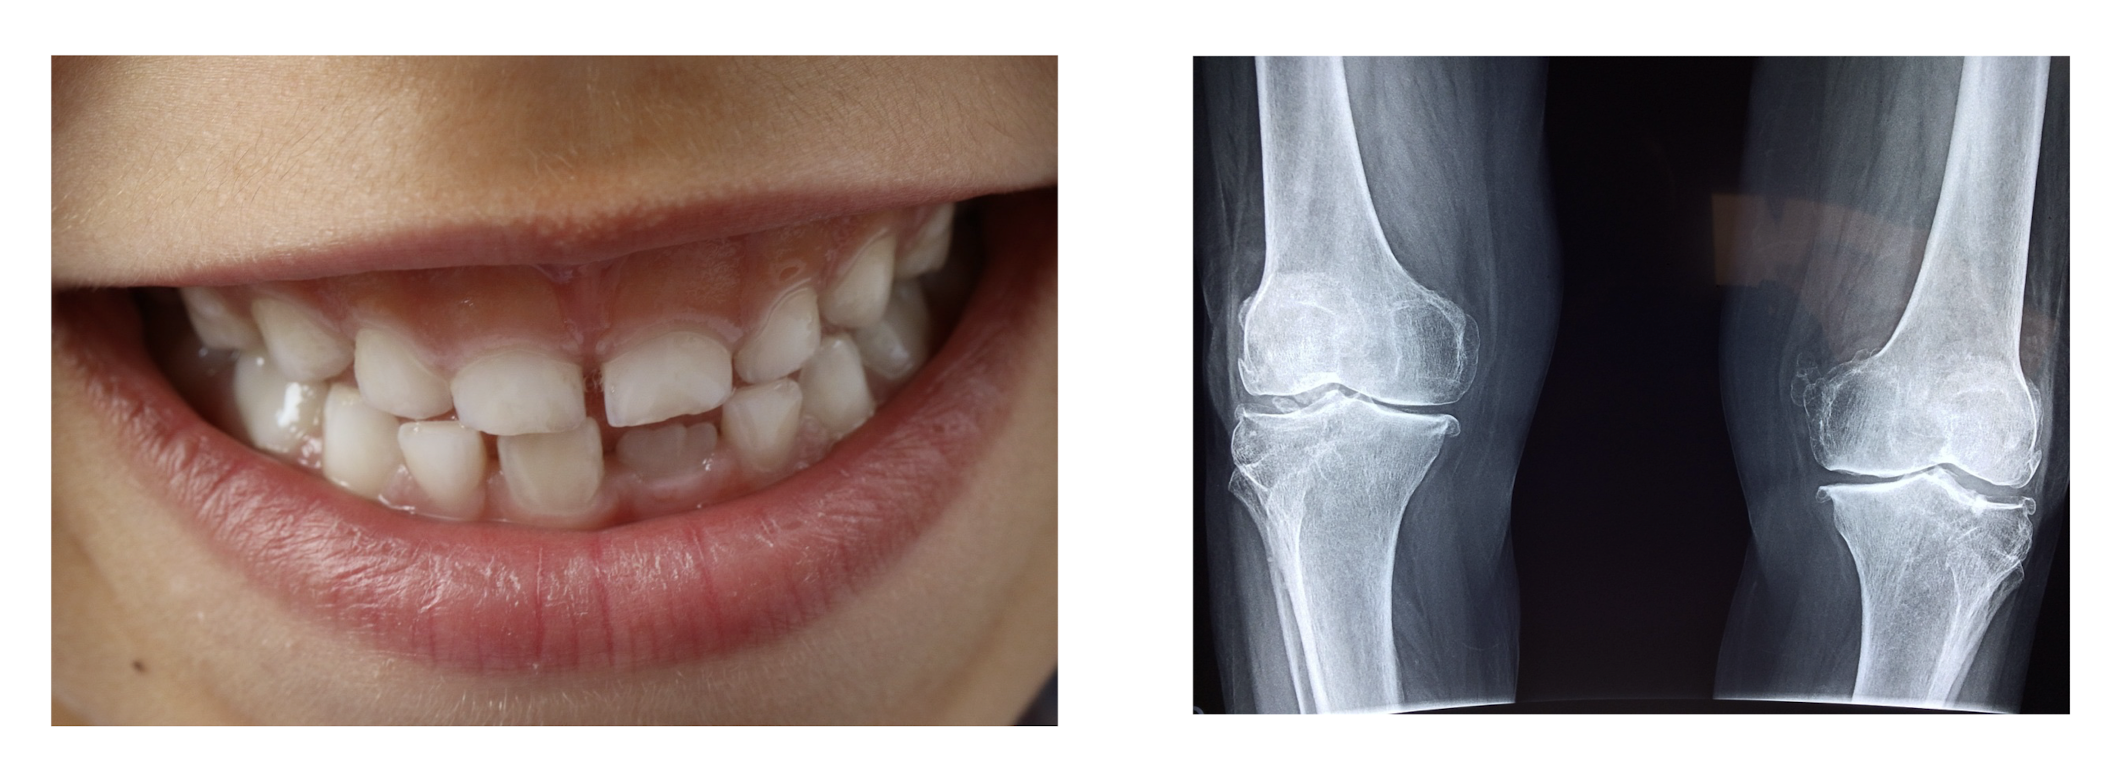

1. 결합조직 형성과 기능 유지에 필요

결합조직의 생성과 유지는 항 괴혈병 작용과 밀접한 관련이 있는데, 이는

정상적인 치아 및 뼈의 형성,

뼈의 손상 회복, 상처치료,

콜라겐 및 연골 형성에 중요하다.

<혹시 내가 비타민C 결핍? 비타민 C의 결핍증상에 대해 알아보자>

주요증상에는 모세혈관의 취약화에 의한 잇몸 또는 피부에서의 출혈,

치아나 뼈의 발육장애, 관절통, 피로감,

점상 또는 반상의 피하출혈, 상처치유의 현저한 지연 등이 있다.